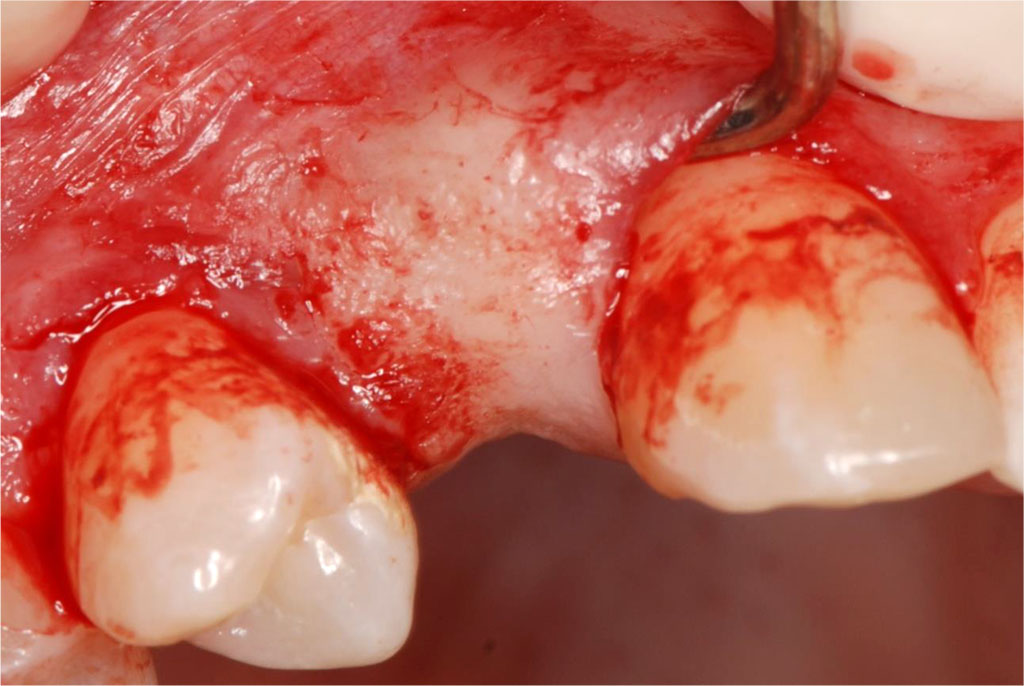

The patient was qualified for peri-implant soft tissue augmentation using the tunnel technique and a subepithelial connective tissue graft (sCTG) taken from the palate. The procedure was discussed, post-operative recommendations were explained and written informed consent was obtained for the procedure. One Shot - 2g of Amoxycyllin was administered 1h before surgery - perioperative antibiotic prophylaxis. Prior to the procedure, the patient had blood drawn from the ulnar vein to obtain Advanced Platelet Rich Fibrin (A-PRF) membranes to secure the donor site located on the palate (Fig.2). Infiltration anaesthesia of the donor site and conduction block anaesthesia of the greater palatal orifice with articaine 1:100000 was administered. With use of preoperatively prepared template (Fig.3), an epithelial-connective tissue graft was harvested from the palate using the free gingival graft (FGG) technique (Fig.4). A larger amount of sCTG was harvested due to the need to simultaneously cover gingival recessions in the left maxillary region. The graft was then de-epithelialised (Fig.5). The donor site wound was secured with an A-PRF membrane and crossed 5-0 non-resorbable mattress sutures (Fig.6). Under infiltration anaesthesia of the recipient site with a 1:100,000 preparation of articaine in area 12-14, a supraperiosteal tunnel was dissected (Fig.7). An sCTG was then inserted into the tunnel (Fig.8) and 6-0 non-resorbable sutures were placed to position and stabilise the graft in the intracoronal position (Fig.9). Oral rinsing with 0.1% chlorhexidine digluconate for 2 weeks, and postoperative instructions were prescribed. Wound toileting was performed at the follow-up visits each time.

Fig.7 Tunnel preparation in the area of 12-14 using a tunneling instrument set. (Helmut Zepf Medizintechnik GmbH, Seitingen-Oberflacht, Germany).